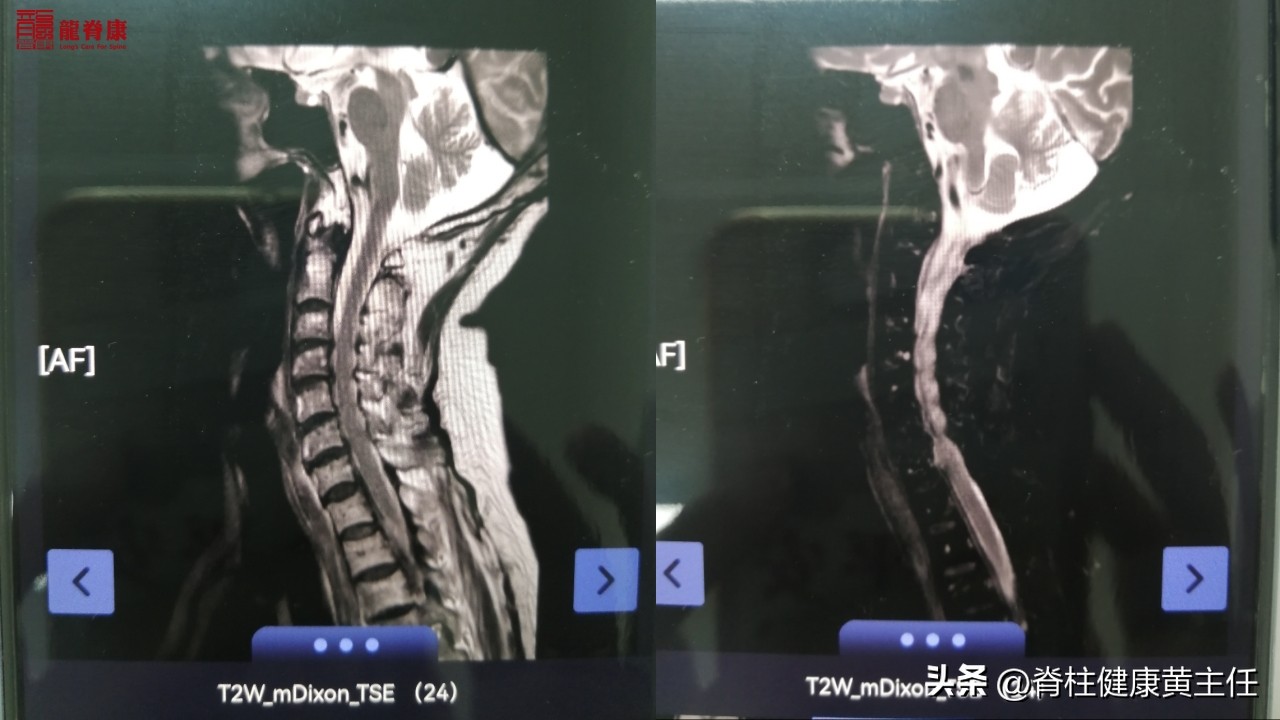

外院颈椎MR专科描述示:

颈椎曲度存在,顺列尚齐。颈椎椎体边缘轻度骨质增生,颈椎椎体及附件信号无异常。颈椎间盘信号在T2W1上普遍减低。颈2/3-6/7椎间盘不同程度向后中央突出,硬膜囊受压,其中颈4/5椎间盘突出较前加,脊髓轻度受压,双侧椎间孔无变窄,神经根无受压。后纵带及黄韧带无增厚,椎管前后无狭窄。脊膜无增厚及无异常信号影,脊髓形态、信号未见异常。椎管内未见异常信号影。

但由于MRI检查显示颈4/5椎间盘突出较前加重,脊髓受压;并且患者年纪较大82周岁,有存在明显的骨质疏松;因此在手法复位上存在安全风险,不适宜做有闪动力的手法正骨复位。但可以进行缓慢的、轻力度(无闪动力)的颈椎关节松动术,解除颈椎上段小关节错位卡压的问题;配合理疗、热疗等,促进颈部血液循环,以缓解头晕不适。